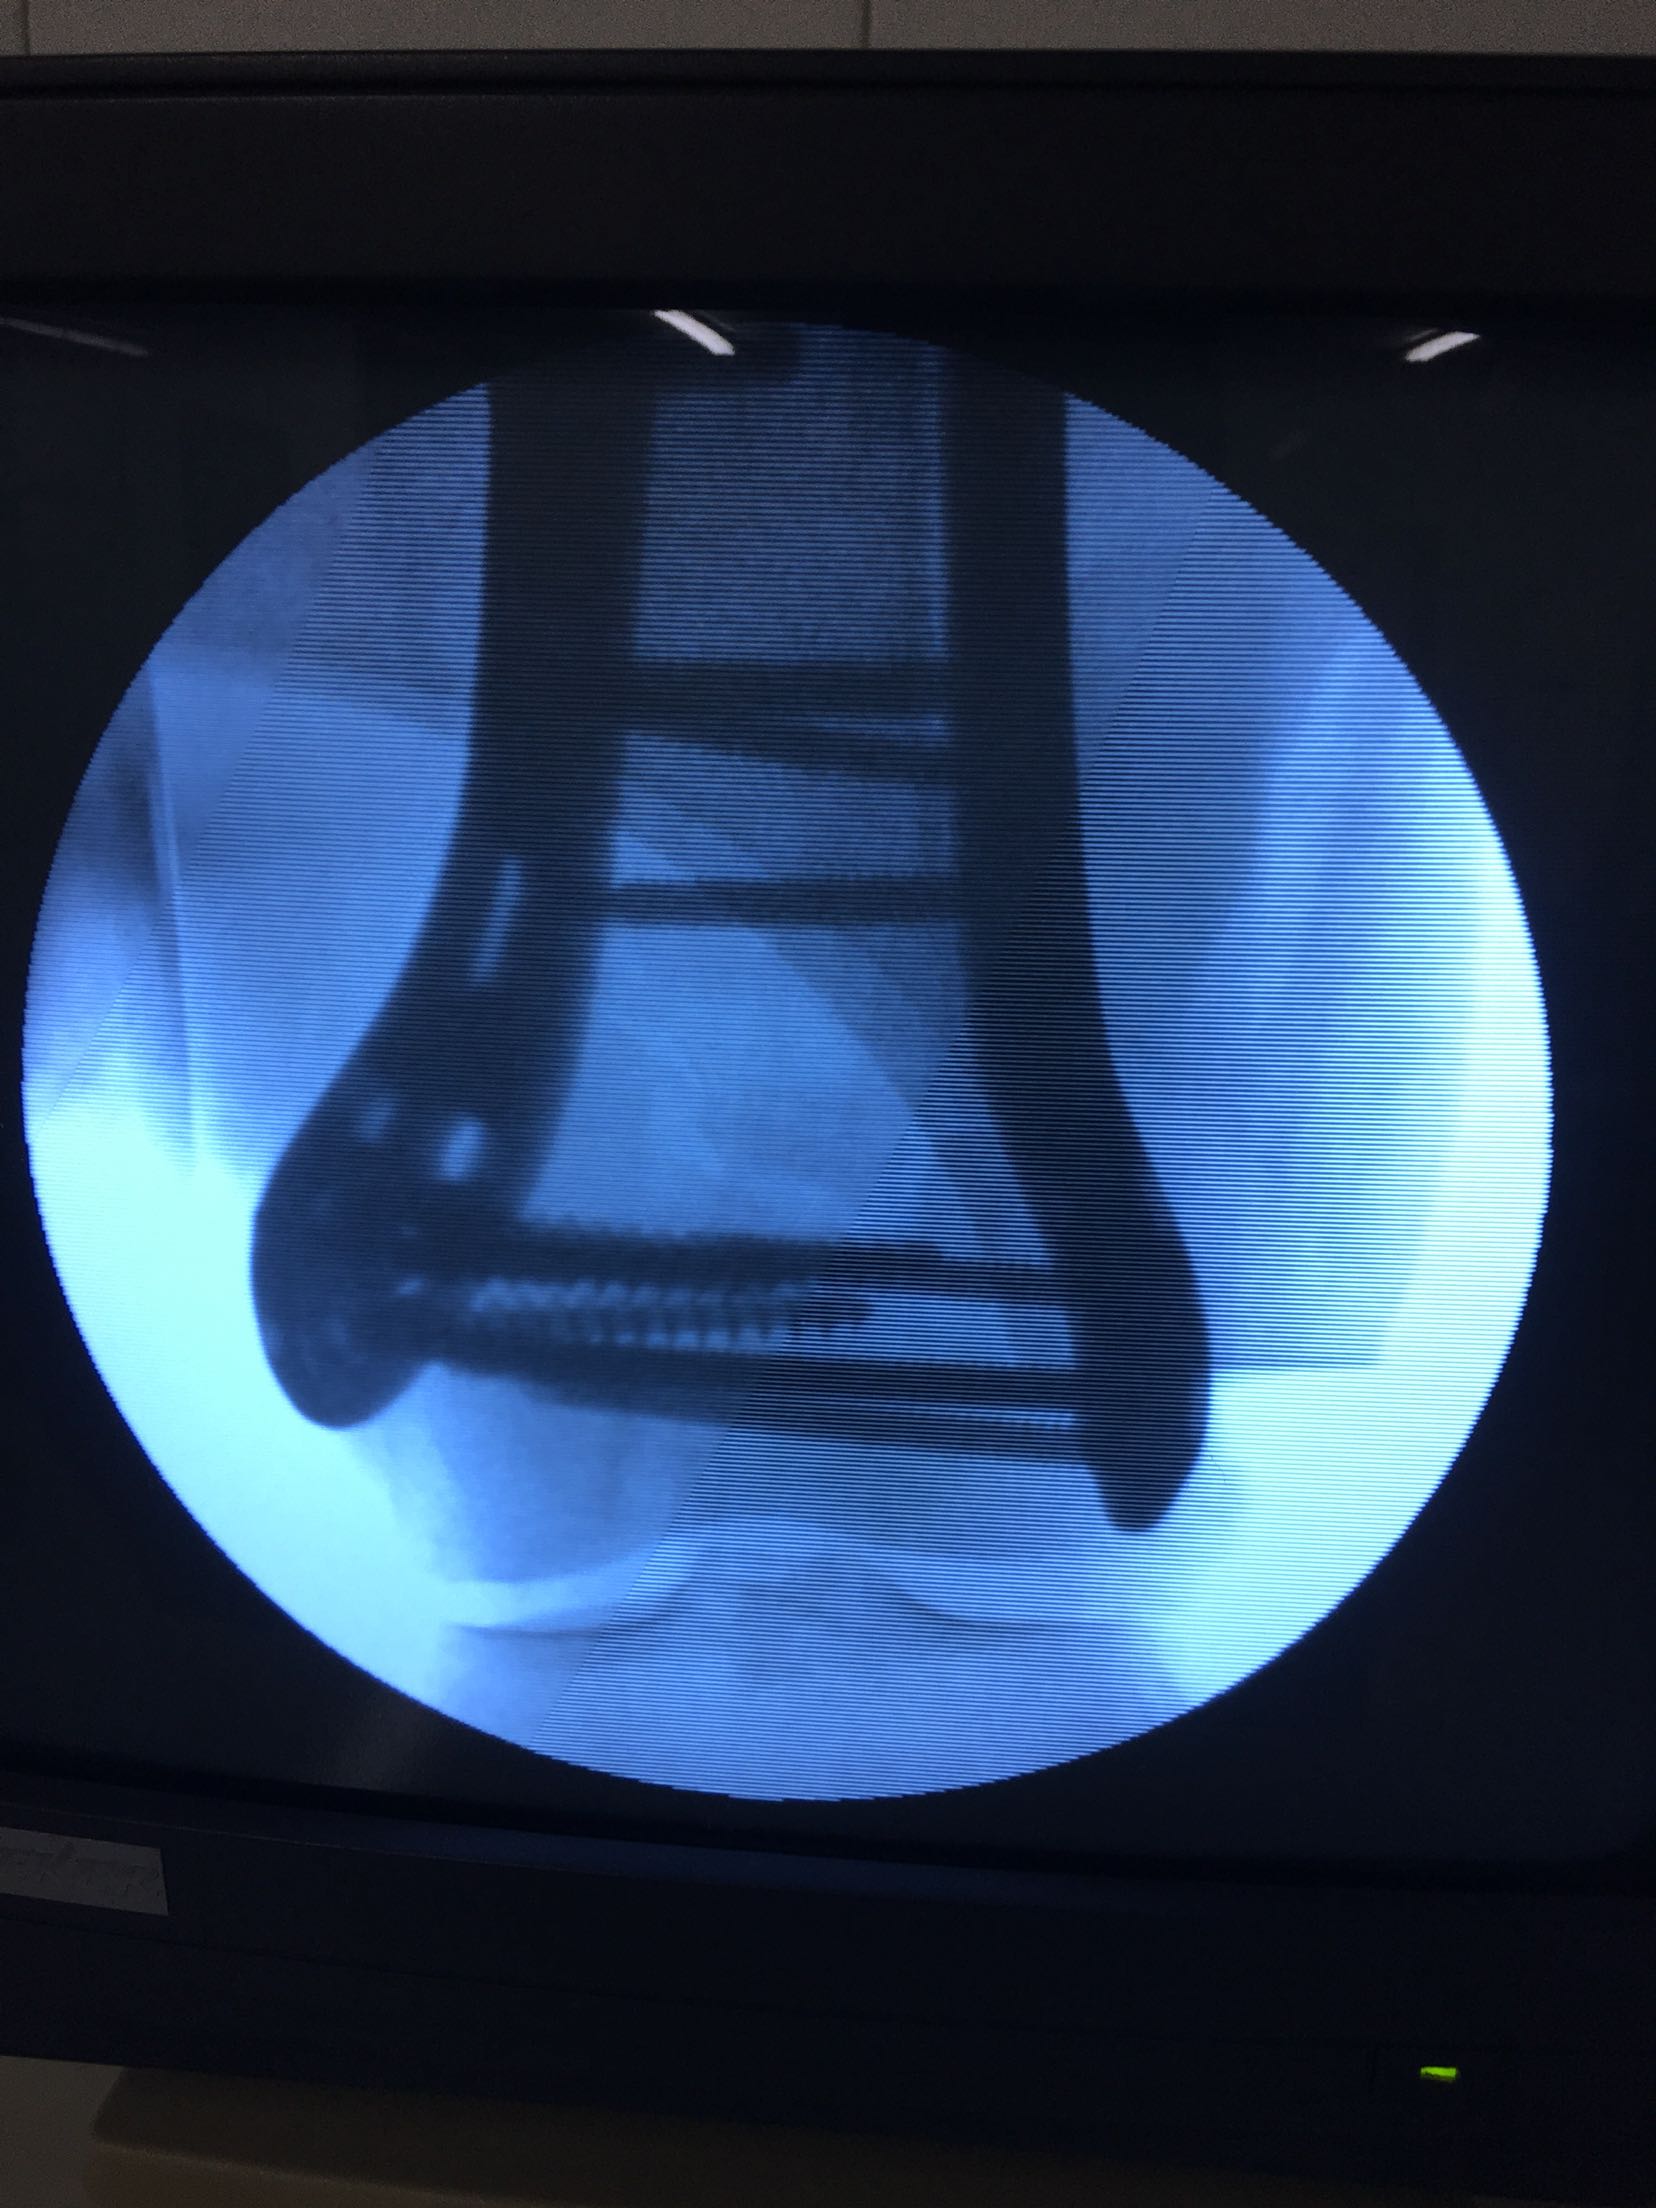

完善检查,急诊在局麻下行胫骨结节骨牵引术。术后一周,病情平稳,在腰麻下行切复内固定术,考虑骨折粉碎,骨质疏松,拟行双钢板固定。术后抗炎,对症治疗,嘱咐一周后早期膝关节微动锻炼。